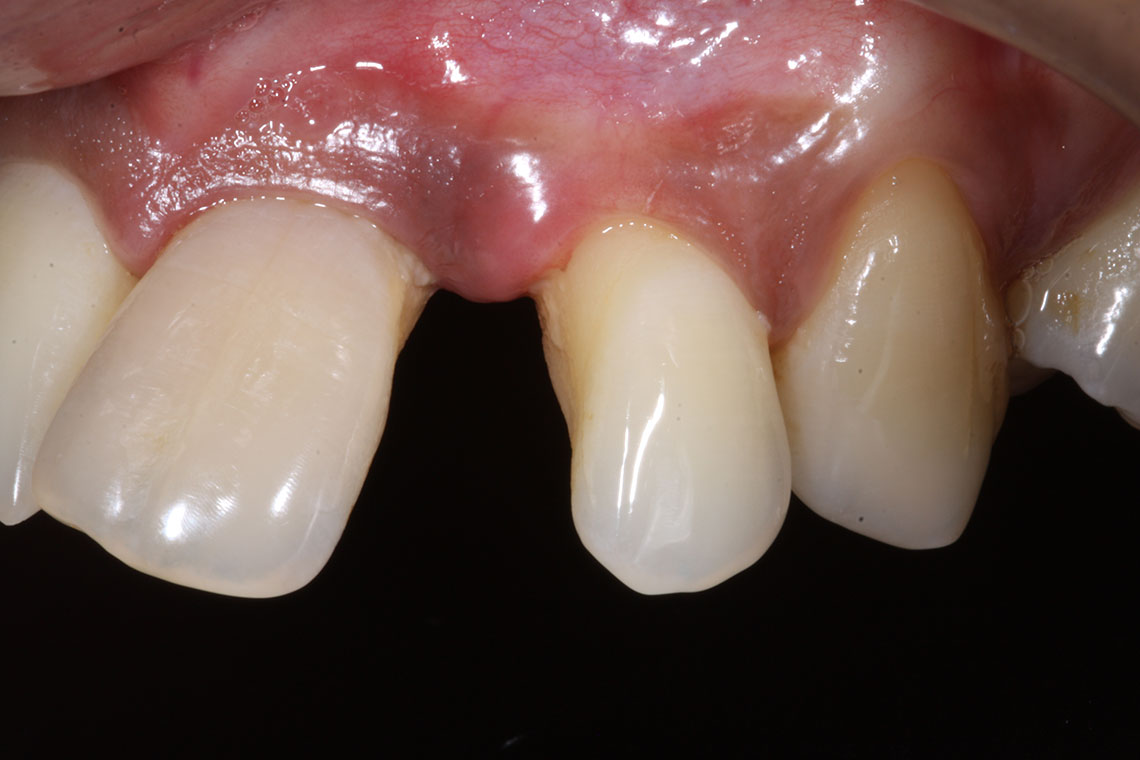

This lovely lady attended with very low confidence due to her teeth and smile. Gum disease and trauma had led to the teeth drifting. One of her front teeth was so loose that it needed to be replaced. We started by providing intensive treatment with our dental hygienist to treat the gum disease. Following this Invisalign® braces were used to align the teeth and the teeth were whitened. A dental implant was then placed to replace the loose front tooth and composite bonding was performed to the adjacent front tooth. The change in the patient’s confidence as a result of this work was breathtaking.